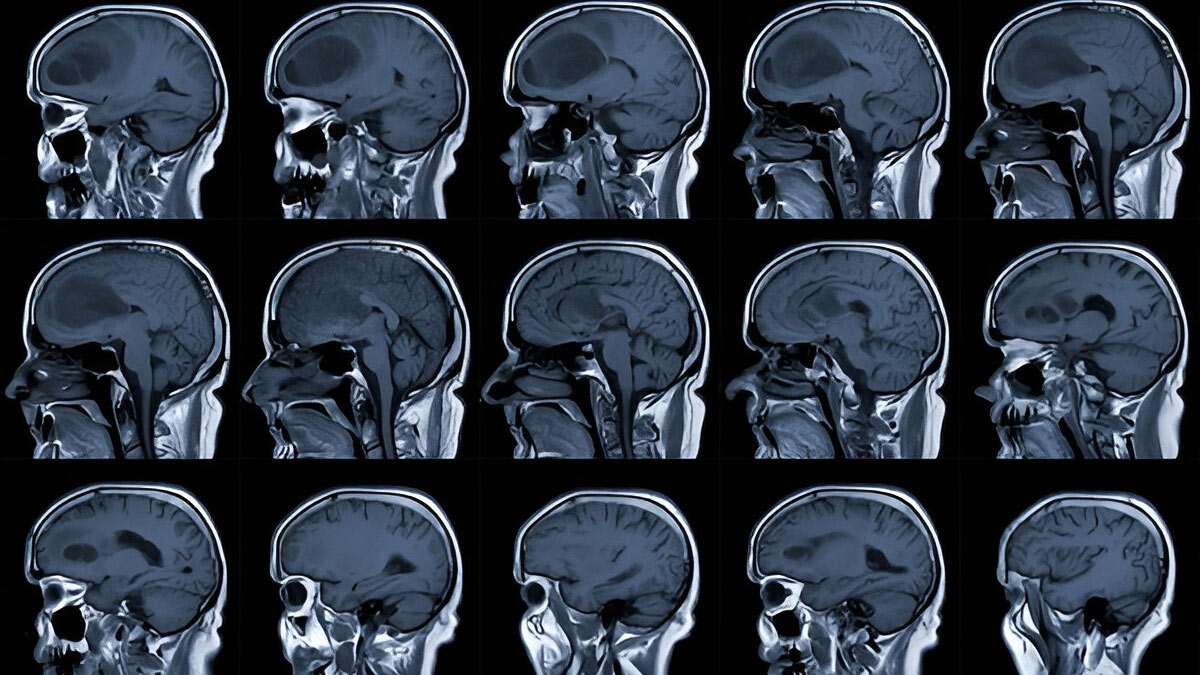

Moli further shared that it was hot but not unbearable. But when she suffered the seizures, a doctor on site told her that it was probably just heatstroke. "We had been in the sun all day, and I hadn't drunk much water, so I sort of thought nothing more of it and that it was probably just heatstroke, and we flew home the next evening," she recalled. Once she was back, she decided to get a second opinion "just to be on the safe side, ”only to find out she had a 4 cm glioma on the left side of her brain.

A glioma is a type of brain tumour that originates in the glial cells of the brain or spinal cord. These cells support and protect nerve cells. Gliomas can be either benign (non-cancerous) or malignant (cancerous) and can vary in their growth rate.

There are three common types of gliomas, which are classified based on their phenotypic cell characteristics: astrocytomas, ependymomas, and oligodendrogliomas.

According to a 2016 study published in Handbook of Clinical Neurology, more than 2.5 lakh new cases of primary malignant brain tumours are diagnosed annually worldwide, 77% of which are gliomas. While anyone can develop gliomas, men are more likely to be diagnosed with them than women.